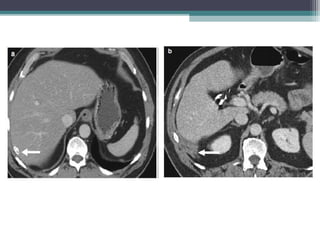

INTRAHEPATIC CHOLANGIO CA

• Late presentation with either a) large well defined mass with

lobular margins b)Purely periductal infiltrating c) Mixed with mass

forming and periductal infiltrating.

• USG:

• Hypoechoic , isoechoic or hyperechoic mass which may be

homogenous or heterogenous .

• CT:

Hypodense solitary mas with satellite nodules

Post con : Thin rim/Thick band of peripheral and patchy

enhancement . The central area of tumour , which contains fibrous

tissues does not enhance during early phase but shows progressive

centripetal enhacement and retension on delayed images during

delayed phase 4-20min ( Helps to dfferenciae from HCC )

• Vascular invasion

• Focal intrahepatic biliary duct dilatation and atrophy

of the segment of the liver drained by these ducts with capsular retraction .

• Since cholangiocarcinoma has no capsule their margins are infiltrative and

difficult to predict on imaging

• MRI:

Irregular heteroechoic mass hypointense on T1 and Hyperintense on T2 wt images